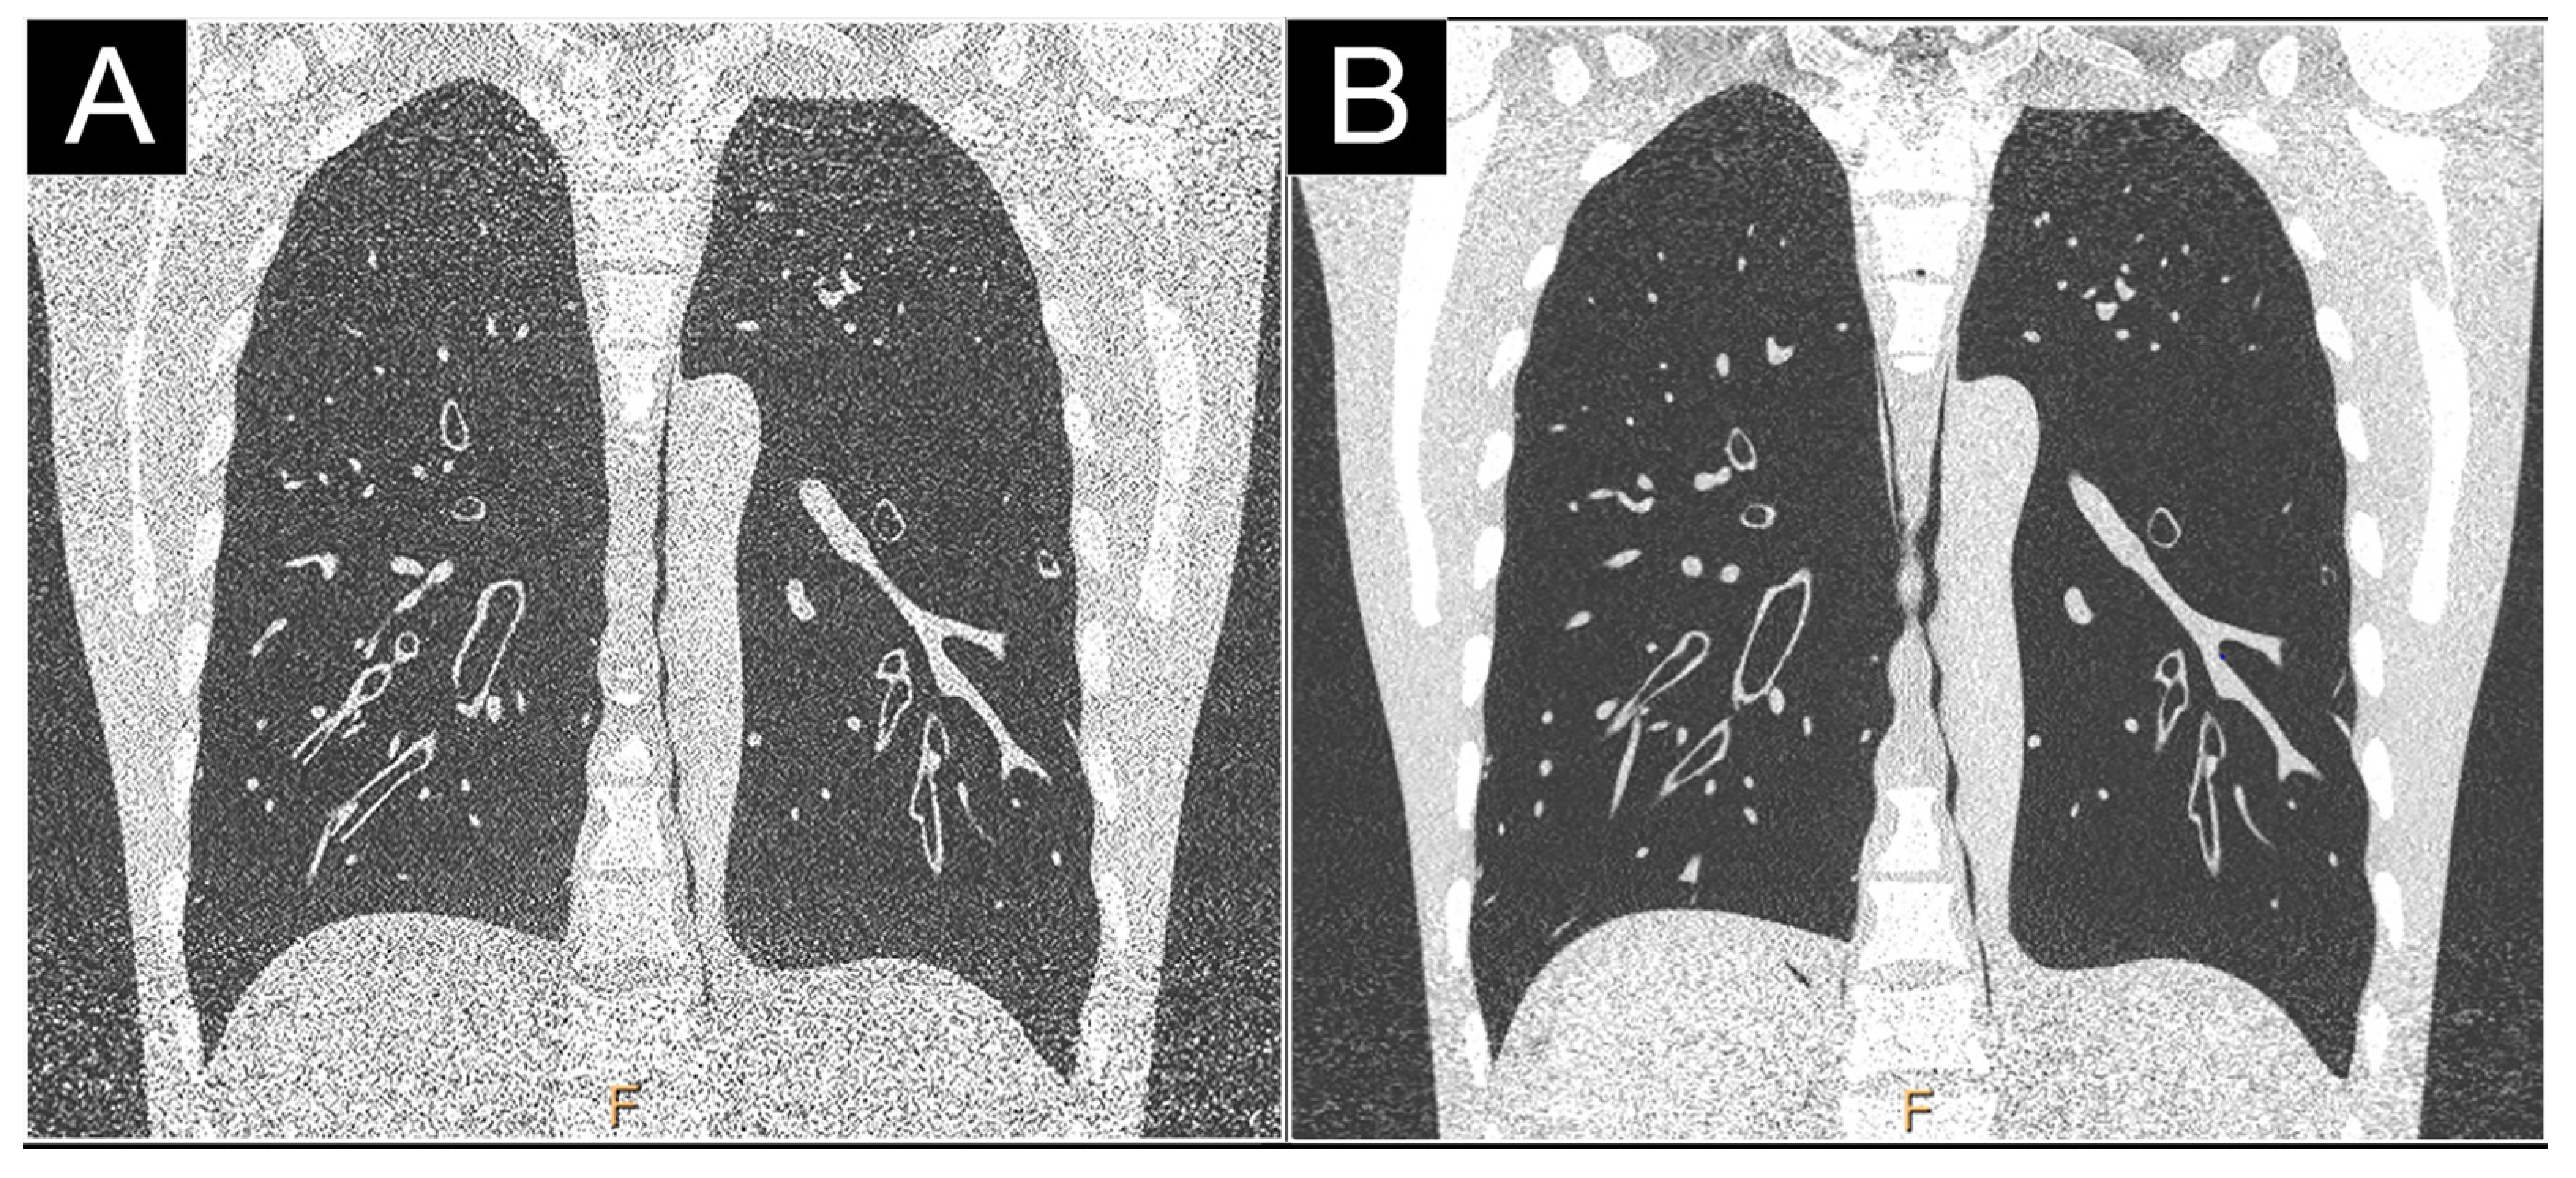

2.2.2. Reduction of Electronic Noise

2.2.5. Dose Efficiency

3.4. Low and Ultra-Low Dose Imaging